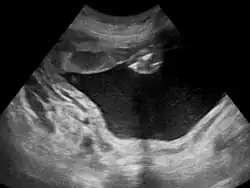

Polyhydramnios is a medical condition describing an excess of amniotic fluid in the amniotic sac. It is seen in about 1% of pregnancies.[1][2][3] It is typically diagnosed when the amniotic fluid index (AFI) is greater than 24 cm.[4][5] There are two clinical varieties of polyhydramnios: chronic polyhydramnios where excess amniotic fluid accumulates gradually, and acute polyhydramnios where excess amniotic fluid collects rapidly.

During the pregnancy, certain clinical signs may suggest polyhydramnios. In the mother, the physician may observe increased abdominal size out of proportion for her weight gain and gestation age, uterine size that outpaces gestational age, shiny skin with stria (seen mostly in severe polyhydramnios), dyspnea, and chest heaviness. When examining the fetus, faint fetal heart sounds are also an important clinical sign of this condition.